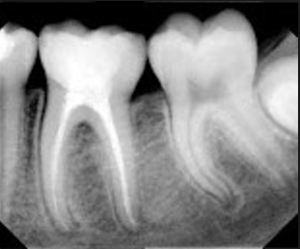

Endodoncia es el tratamiento de conductos radiculares, esto corresponde a toda terapia que es practicada en el complejo dentina-pulpar.

La terapia endodóntica consiste en la extirpación total de lapulpa dental (nervio-arteria-vena) Se aplica en piezas dentales fracturadas, con caries profundas o lesionadas en su tejido pulpar.